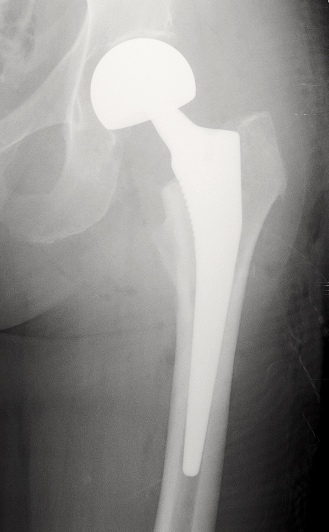

2. PTH

INDICATIONS:

• Arthrose (N°1)

• ONA

• Dysplasie

• Fracture du col

- Scellées avec du ciment chirurgical, ou recouverte d’hydroxyapatite (intégration à l’os)

- Couple de frottement: métal, céramique ou polyéthylène

- Tiges longues ou courtes

- Double mobilité: un insert entre la tête et la cupule